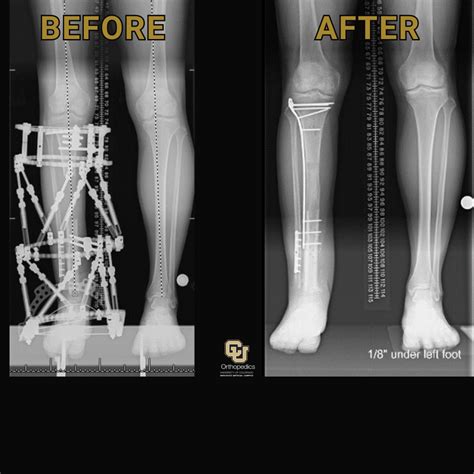

At its core, leg lengthening surgery, medically known as distraction osteogenesis, relies on the body’s innate ability to regenerate new bone and soft tissue. The process begins with an orthopedic surgeon making a precise cut in the bone, known as an osteotomy. Once the bone is divided, a specialized device, usually an internal intramedullary nail, is implanted into the marrow cavity.

After the initial surgery, a period called the "distraction phase" begins. During this time, the device is gradually lengthened—often via an external remote control—by a small amount each day, typically about one millimeter. This slow separation creates a gap where new bone tissue, nerves, and blood vessels slowly form to bridge the space. Following the distraction phase, the bone must undergo a consolidation phase, where the newly formed bone mineralizes and hardens to reach full strength.

Once the bone has fully consolidated and the patient has completed the rigorous physical therapy required, the results are typically permanent. Many patients report significant improvements in confidence and, in the case of medical corrections, a noticeable improvement in gait and overall quality of life. However, it is vital to keep expectations grounded in reality. The body takes a long time to adapt to a new skeletal structure, and while height gains of several inches are possible, the journey requires resilience, dedication, and a deep understanding of one's own physical boundaries.